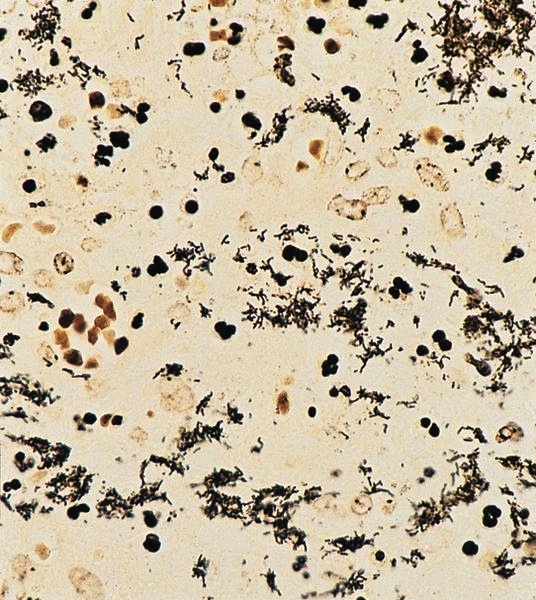

Mycobacterial spindle cell pseudotumor

Definition / general

- HIV+ patients, often involvement of many sites

- Also infants after

- bCG vaccination (Zhonghua Bing Li Xue Za Zhi 2001;30:89)

- Posttransplant (Am J Clin Pathol 1985;83:524)

- Spindle cells are macrophages with large amounts of mycobacteria (Am J Surg Pathol 1992;16:276)

- Intraoperative touch imprints may demonstrate numerous intracellular organisms (Arch Pathol Lab Med 1995;119:811)

Microscopic (histologic) description

- Nodes show partial / complete effacement by storiform pattern of bland spindle cells, some with vacuoles

- Numerous vessels lined by plump endothelial cells, plasma cells and lymphocytes

- No multinucleated tumor cells, no foamy histiocytes

Microscopic (histologic) images

Contributed by AFIP and Chunyu Cai, M.D., Ph.D. (Case #532)

Cytology description

- Spindle cell proliferation resembling Kaposi sarcoma; no foamy histiocytes (Acta Cytol 1995;39:125)

Positive stains